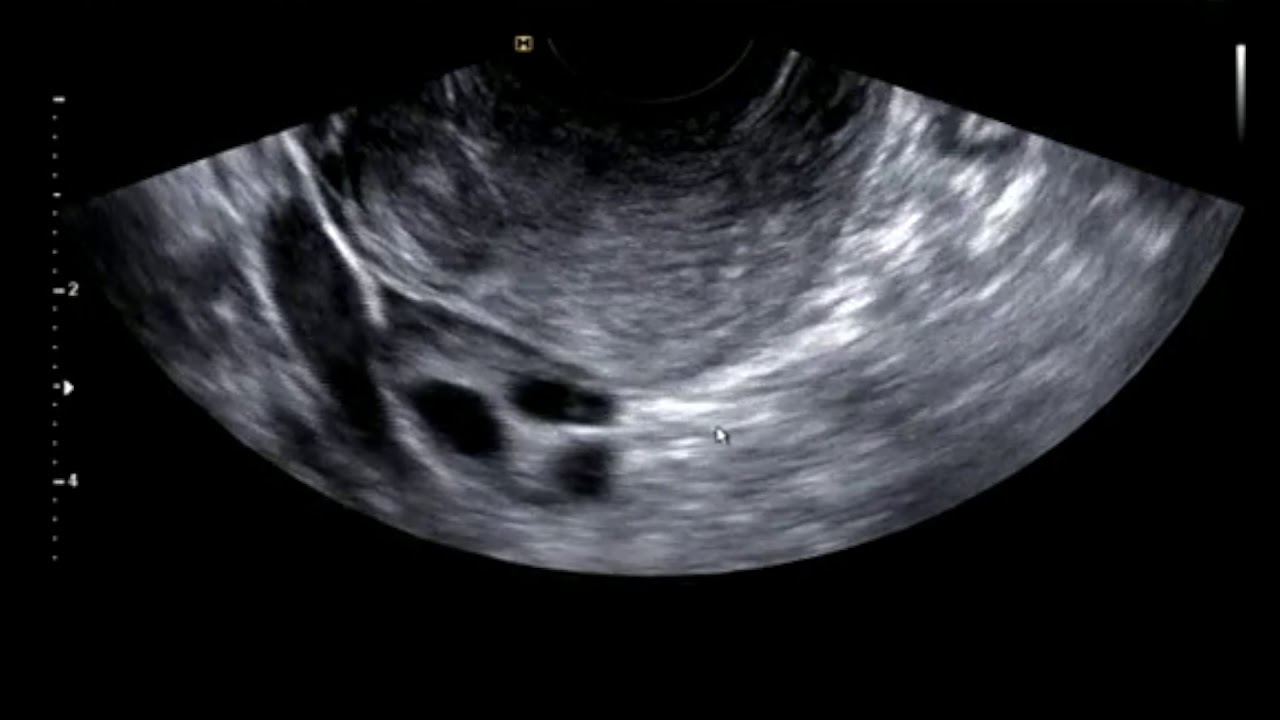

자궁 근종의 초음파 동영상

자궁 근종의 실제 초음파 영상입니다. 자궁 근종은 중년 부인들에게서 흔한 질병이지만 요즘 젊은 여성에서도 드물지 않게 나타나는 병입니다. 자궁 근종을 수술해야 하는 경우와 치료 방법들에 대하여는 영상의 끝부분에서 자막으로 간단히 적어 놓았습니다. 영상의 유튜브 게시에 동의하여 주신 분께 감사드립니다.